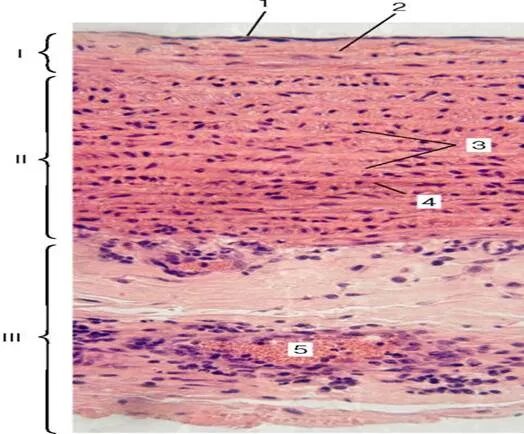

Артерия эластического типа препарат гистология